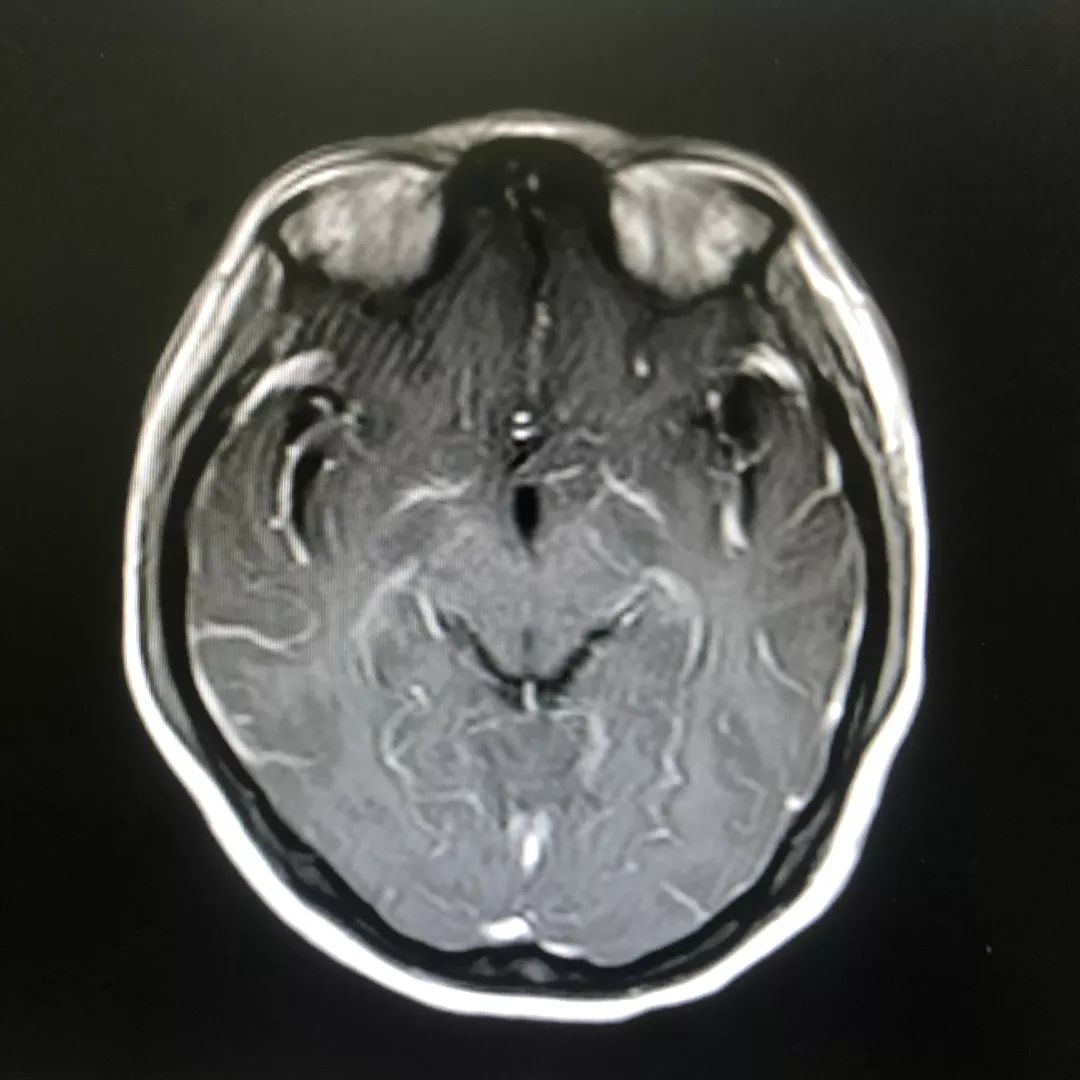

根据林女士发热、头痛,且出现精神行为异常、局部神经功能受损,查体可见明显的脖子僵硬,转颈和低头困难等症状,以及腰椎穿刺术及头颅磁共振增强检查等检查结果,医院神经内科专家高度怀疑结核性脑膜炎(一类难确诊、高病死率的疾病)可能,并立即启动了抗结核治疗。

头颅增强磁共振:脑膜多发线样增强影